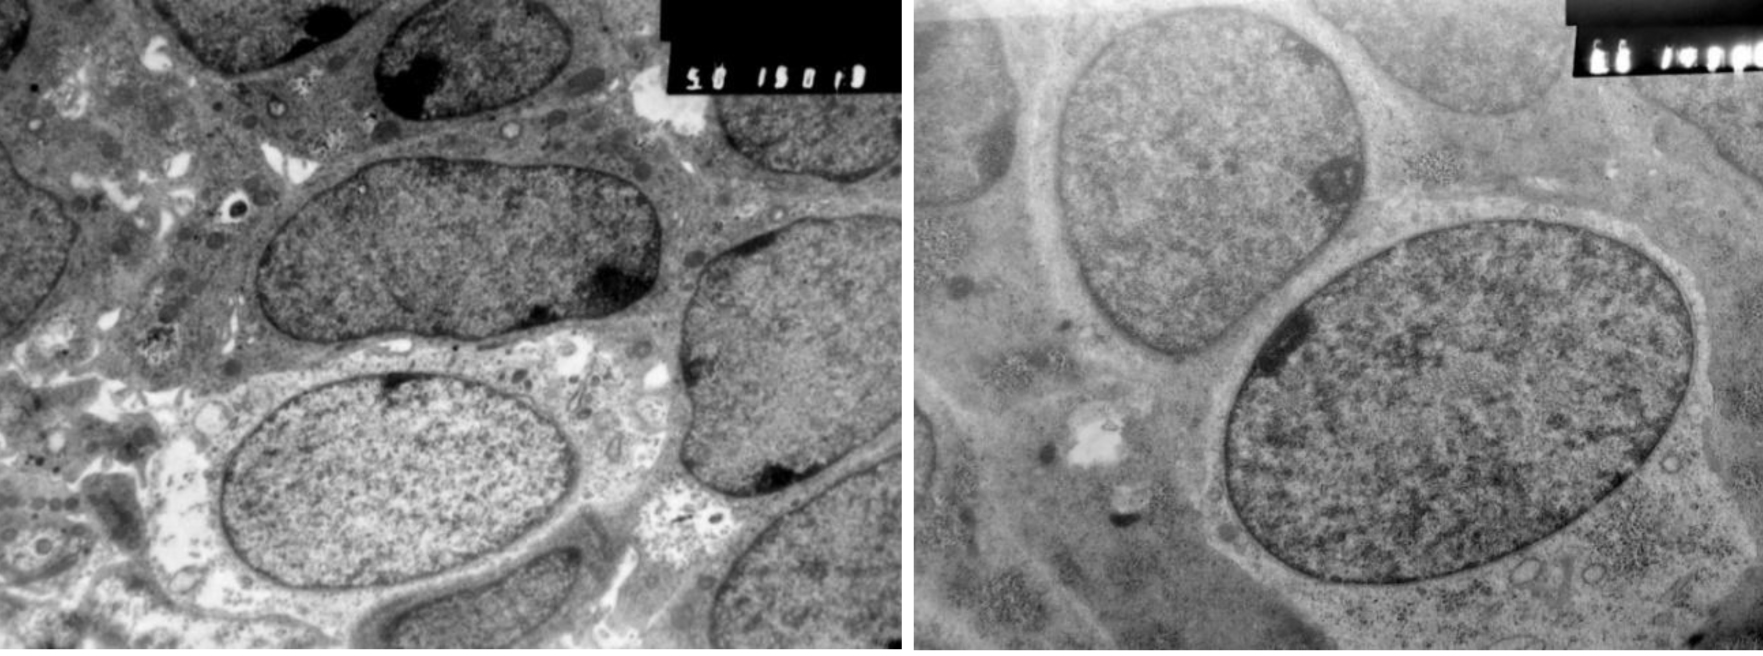

Рис. 4. Эмбрион человека. Биологический возраст 44–46 суток. Зона перехода стомодеального эпителия в карман Ратке. Стрелки – участок с апоптозом эпителия, МК – мезенхимальные клетки, ЭК – эпителиальные клетки стомодеума. Электроннограмма, ув. ×4000. Шкала – 10 мкм

Начиная с 15 СК в эпителии КР выявляются мерцательные клетки и макрофаги моноцитарного генеза. Эпителий преобразуется в полидифферонную структуру. В составе выстилки передней, а затем дна и задней стенки КР, начиная с 19 СК, выявляются дифференцирующиеся аденоциты и аденотропоциты (рис. 5).

Рис. 5. Аденотропоциты в составе эпителия кармана Ратке. Тиреотропоцит (слева), гонадотропоцит (справа). Электроннограмма, ув. ×8000